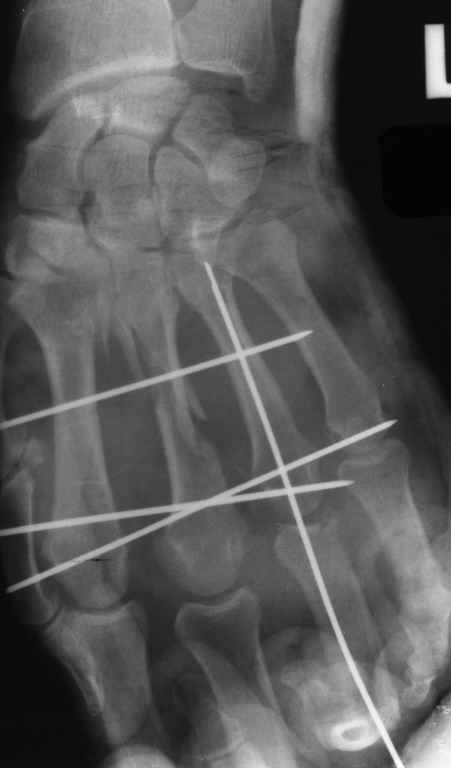

Диагноз: Стойкая Смешанная дермотеногенная контрактура 3,4 пальца правой кисти.

Судя по выписному эпикризу, рентгенограммам и фотографиям, пациенту

показано этапное лечение.